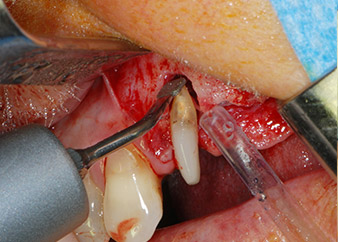

Un mes después, en el día de la intervención, el dolor y la inflamación se habían reducido al mínimo en la pieza 24, pero seguía habiendo una movilidad de clase II de Miller. Después de la apertura de los colgajos y de la limpieza del tejido infectado periapical y perirradicular, la extensión del defecto óseo quedó evidente (figuras 2 y 3).

la raíz bucal de la pieza 24 mostraba una pérdida total del hueso y de la fijación

Fig. 2 y 3: Después de abrir los colgajos, un mes después de realizar la revisión endodóntica y de iniciar la terapia periodontal en toda la boca, la raíz bucal de la pieza 24 mostraba una pérdida total del hueso y de la fijación.

En primer lugar, en un intento por gestionar el problema endo-periodontal, el resto de la superficie radicular se desbridó con cuidado con un equipo piezoeléctrico (Piezomed de W&H, utilizado con el inserto S1 con forma de espátula, concebido en un principio para la erosión de la pared lateral del seno) (figura 4). A continuación, el ápice se erosionó con el mismo instrumento para eliminar el tejido apical infectado residual y reducir las posibles ramificaciones accesorias del canal radicular (apicectomía) (figura 5). No fue necesario realizar un retrorellleno, puesto que la obturación ortógrada se acababa de revisar.

Fig. 4: Para conservar el diente como un pilar provisional, el periodontio se desbridó utilizando un equipo piezoeléctrico...